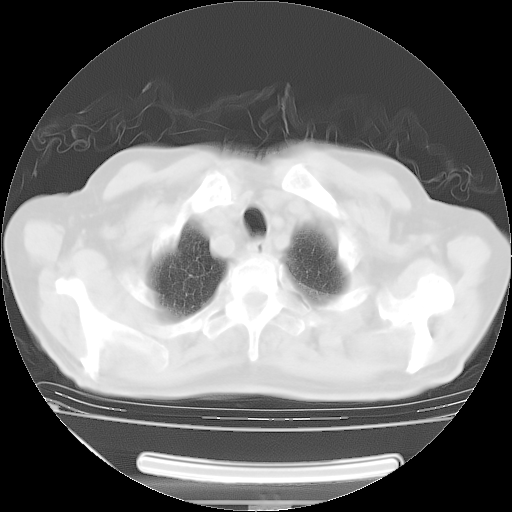

今天复查肺部CT,发现双肺广泛磨玻璃样改变。所以我把3月19日和5月9日相隔50天的肺部CT上传。请大家会诊。

5月9日肺部CT(在4月27日齐鲁医院肺部CT描述部分肺组织磨玻璃样改变,12天后肺组织广泛磨玻璃样改变)

大致读了系列胸部CT:纵隔窗无明显异常,肺窗:从4、27至今:主要是双肺中下野外带可见毛玻璃样改变,目前处于急性肺泡炎阶段,至于原因考虑1、结替组织或胶原血管性疾病所致?2、恶性疾病如恶组在肺部所致的表现或细支气管肺泡癌?3、药物或其它原因如肺蛋白沉着症所致肺泡炎目前不太可能?总之,明天就去请我院的呼吸科、感染科、血液科和临免专家会诊哈。